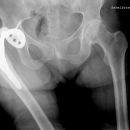

HüftTEP Luxation